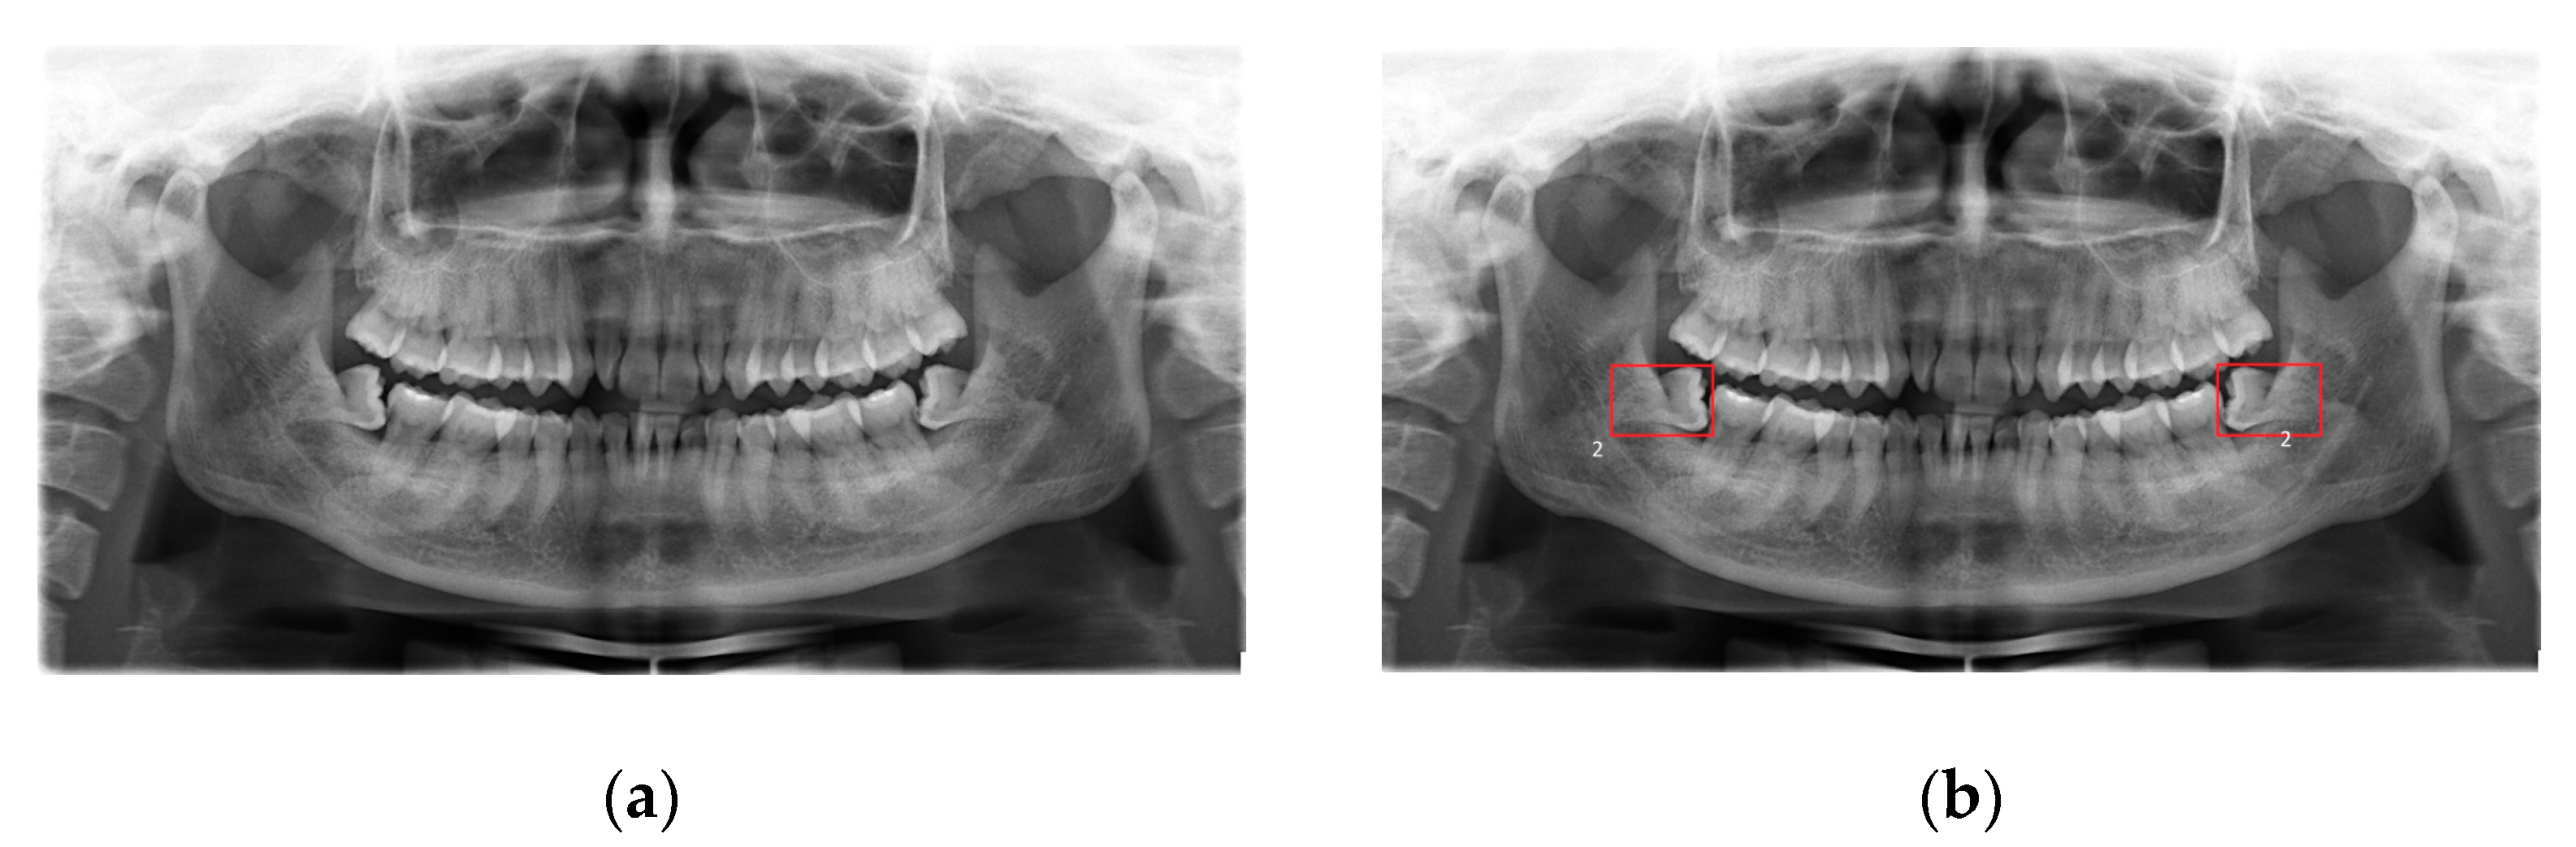

Table 3. Gangthep Hospital and Thai Nguyen National Hospital data summary. - The fourth dataset is the real dental dataset from Hanoi Medical University Hospital, Vietnam [53], in which dentists provide a properly labeled dataset that consists of 447 X-ray images with the disease of wisdom teeth deviate and 200 X-ray images without wisdom teeth deviate. The dental experts are from Hanoi Medical University and are currently working as professional dentists (Figure 3).

Figure 3. (a) A dental image. (b) The patient’s cavity area image.

From this, we extract the following features: Gradient (GRA) [54]; Local Binary Patterns (LBP) [55]; Patch [56]; and Entropy, Edge-Value, and Intensity (EEI) [57] (Table 4). The input is an image, and the output is the label of disease or not.